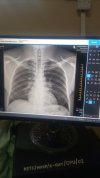

Niupande wa kulia nikivuta pumzika nyingi ndani nahisi Kama kujitonesha kwa ndani naomba ushauli nilipiga x-ray lakini haikuonyesha tatizo. Nikicheka kwa nguvu au kukohoa chini ya kwapa kwenye mbavu kwa ndani kunauma

• IMG_20240919_153436_6.jpg

IMG_20240919_153436_6.jpg

• IMG_20240919_145757_4.jpg

IMG_20240919_145757_4.jpg